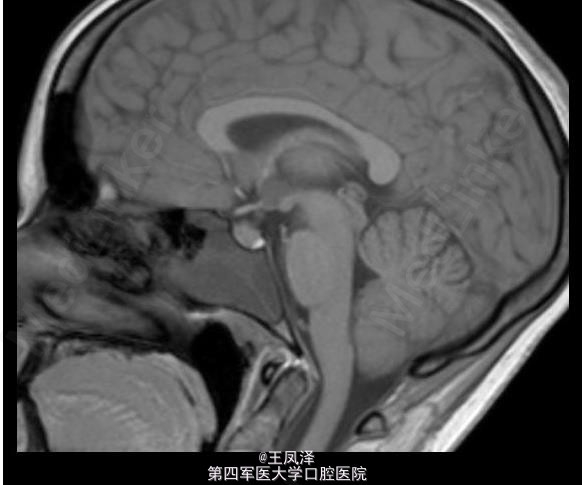

蝶窦粘液囊肿一例

女性,20 岁,在 18 个月大时诊断为自闭症和智力迟钝,目前发生多次抽搐现象,可能为癫痫发作。